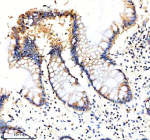

Immunohistochemical staining of EIF3H using anti-EIF3H antibody. EIF3H was detected in a paraffin-embedded section of human colon cancer tissue. Heat mediated antigen retrieval was performed in EDTA buffer (pH 8.0, epitope retrieval solution). The tissue section was blocked with 10% goat serum. The tissue section was then incubated with 2 ug/ml rabbit anti-EIF3H antibody overnight at 4oC. Peroxidase Conjugated Goat Anti-rabbit IgG was used as secondary antibody and incubated for 30 minutes at 37oC. The tissue section was developed using an HRP secondary and DAB substrate.

Immunohistochemical staining of EIF3H using anti-EIF3H antibody. EIF3H was detected in a paraffin-embedded section of human colon tissue. Heat mediated antigen retrieval was performed in EDTA buffer (pH 8.0, epitope retrieval solution). The tissue section was blocked with 10% goat serum. The tissue section was then incubated with 2 ug/ml rabbit anti-EIF3H antibody overnight at 4oC. Peroxidase Conjugated Goat Anti-rabbit IgG was used as secondary antibody and incubated for 30 minutes at 37oC. The tissue section was developed using an HRP secondary and DAB substrate.